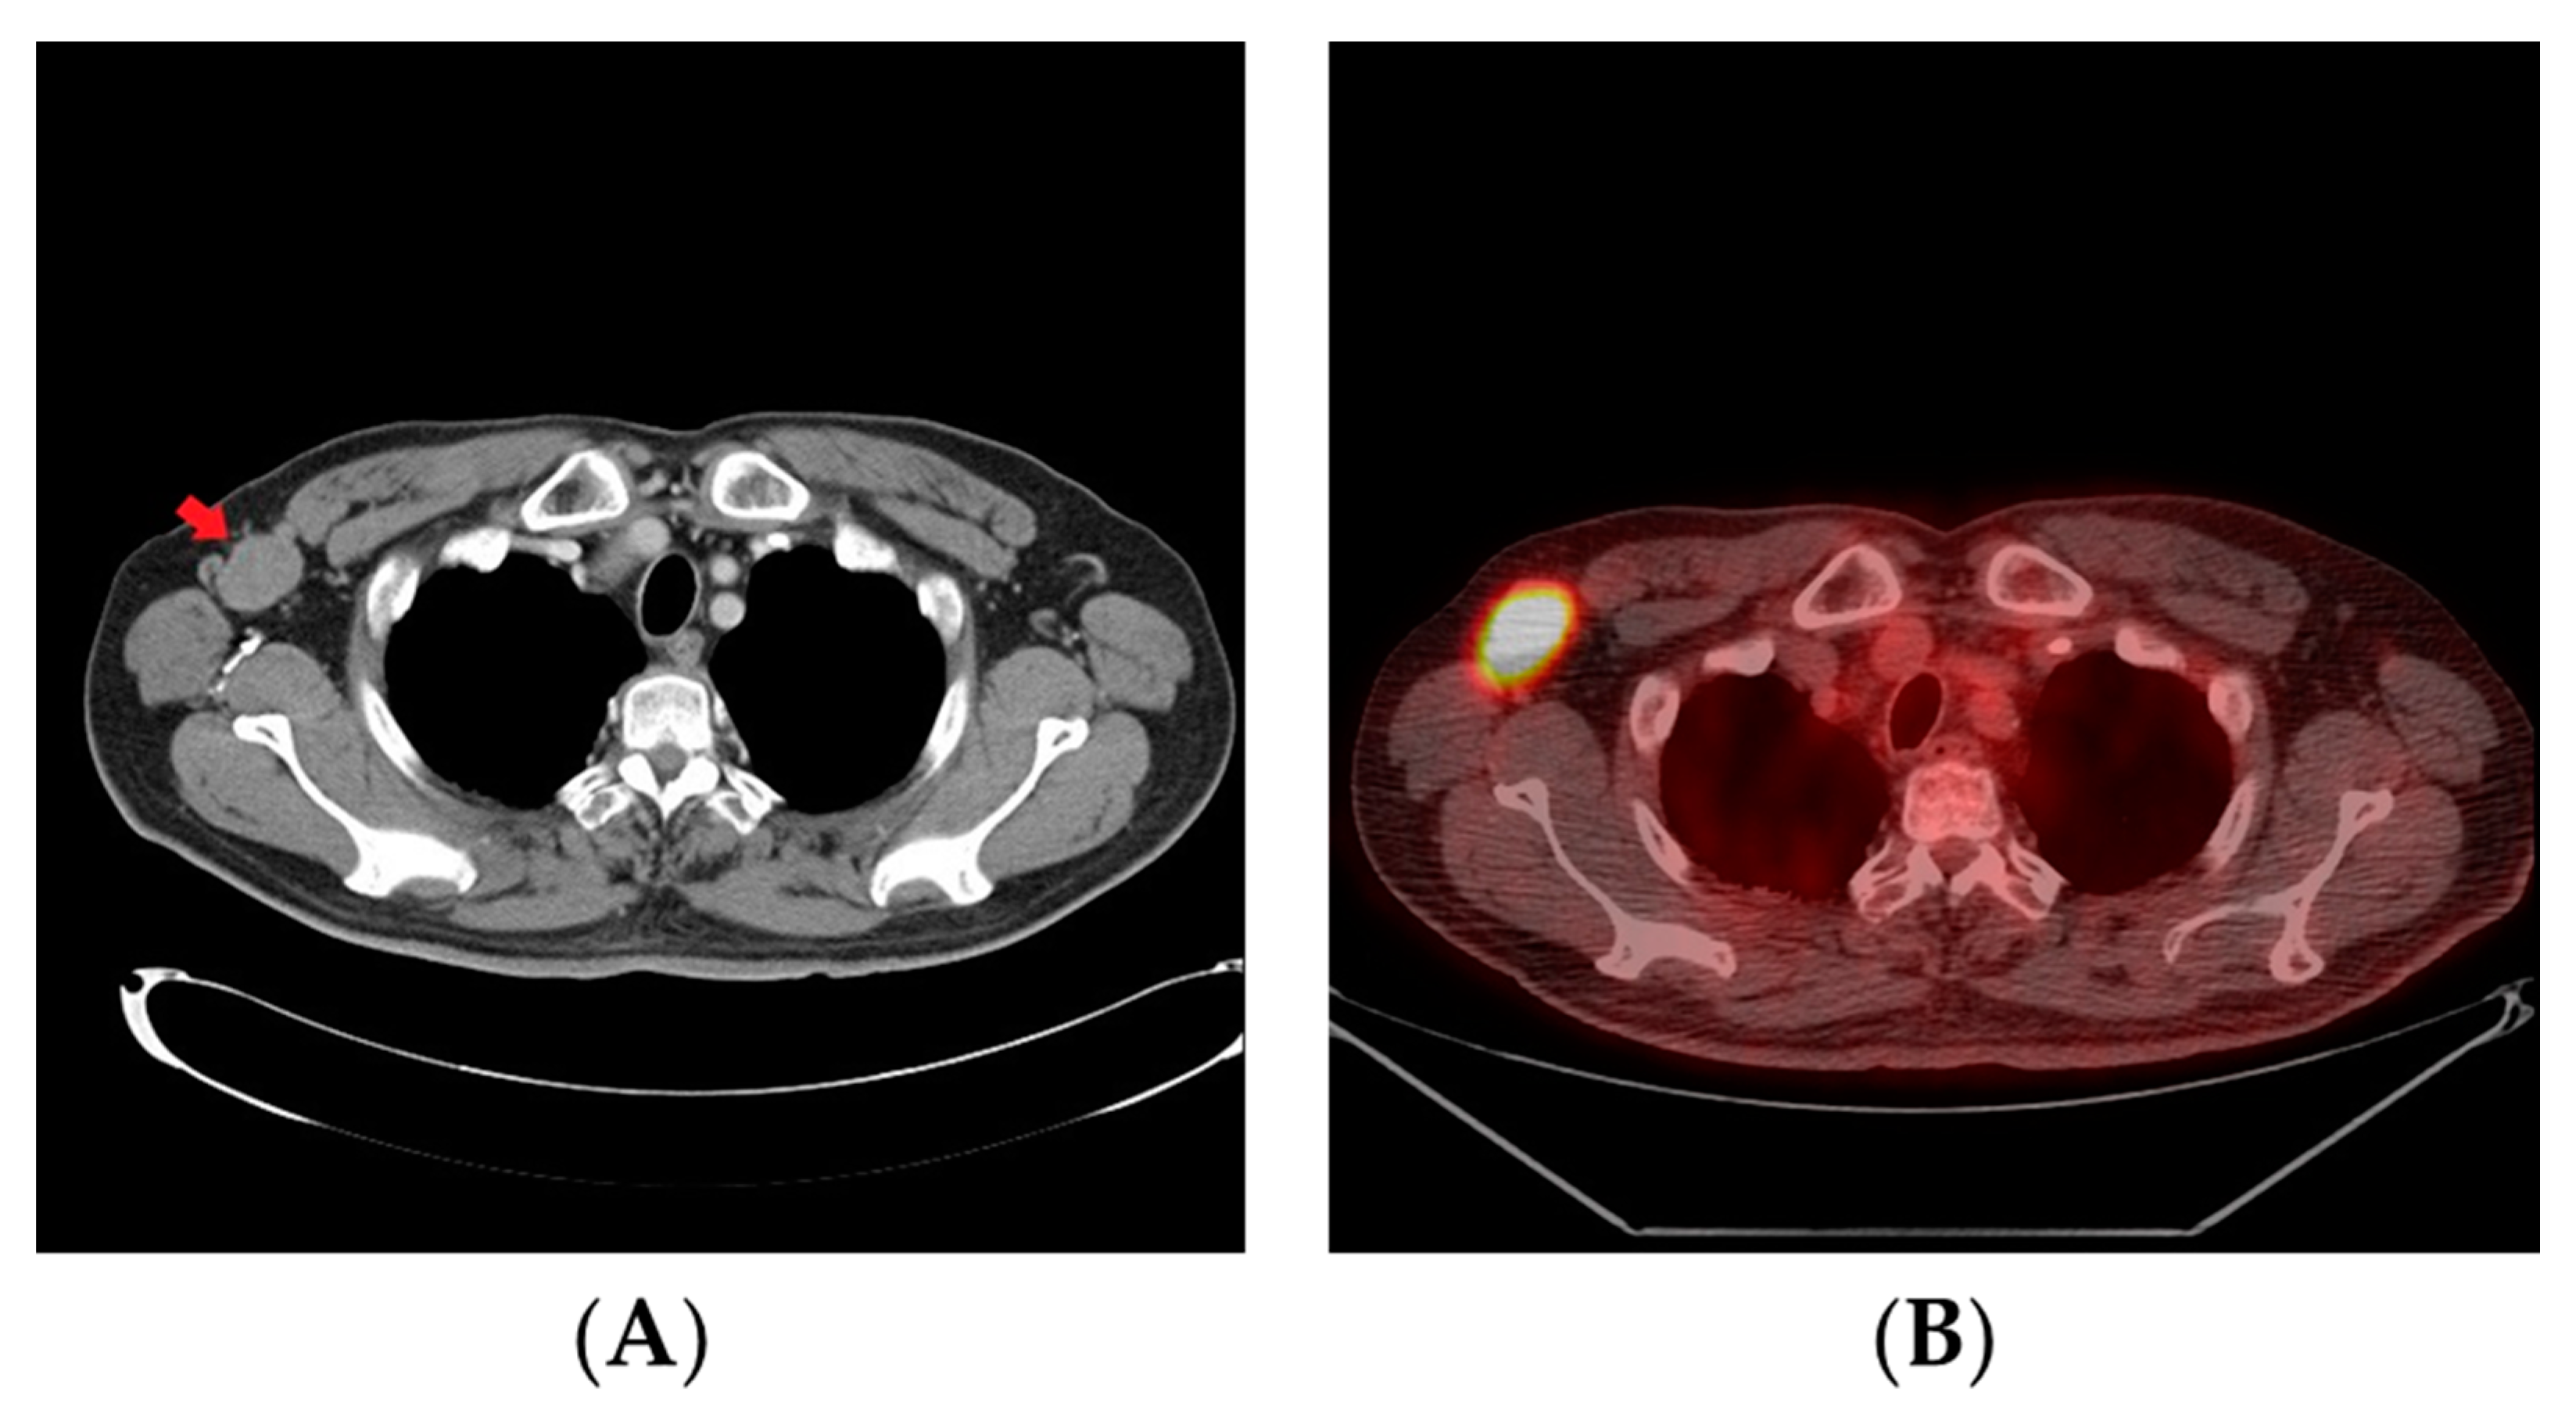

2. Case Report